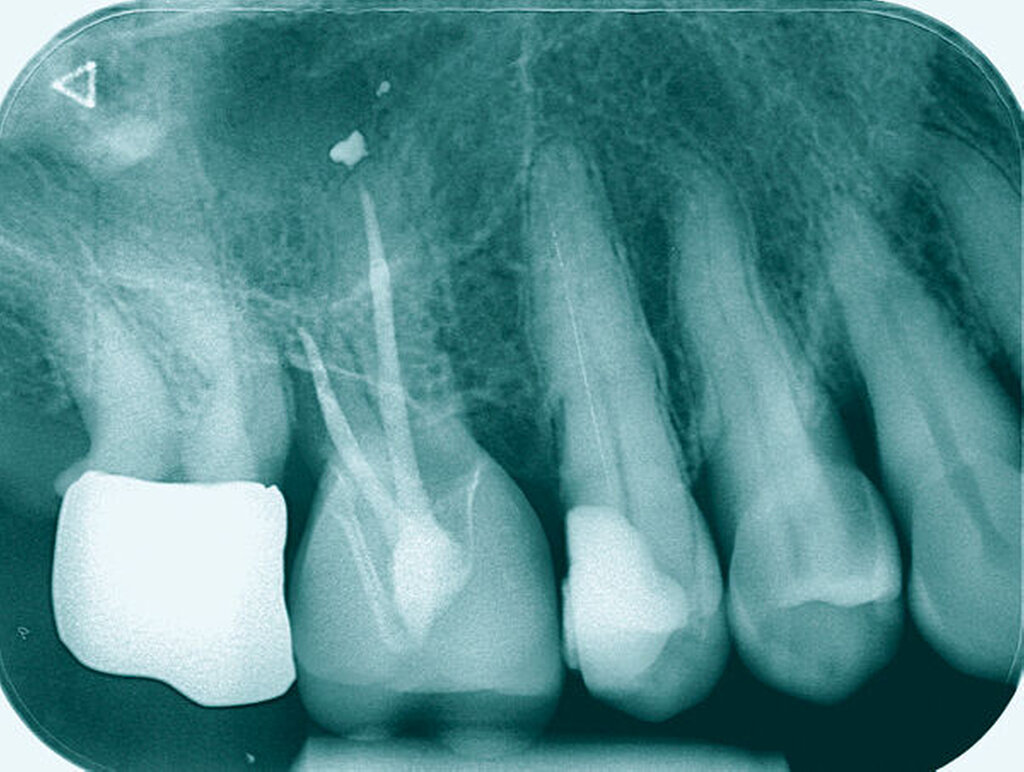

Längsfraktur in die palatinale Wurzel (Fall Nr. 3)

Eine 22-jährige Patientin stellte sich erstmals im Sommer 2017 mit rezidivierenden Beschwerden an dem alio loco endodontisch behandelten Zahn 16 vor. Nach ausgiebiger Aufklärung über die Therapieoptionen bei Verdacht auf einen unbehandelten mb2 erfolgte die Revisionsbehandlung des Zahnes mit der Empfehlung, diesen aufgrund des großen Substanzdefekts zur Stabilisierung zeitnah zu überkronen. Bevor die Überkronung durchgeführt werden konnte, frakturierte der palatinale Höcker. Bei der Inspektion unter dem Operationsmikroskop war sichtbar, dass sich die Fraktur als Längsfraktur in die palatinale Wurzel fortsetzte. Mit der Patientin wurden nun die Optionen der Teilamputation der frakturierten Wurzel oder alternativ der Extraktion des Zahnes besprochen. Sie entschied sich für den Erhaltungsversuch.

Darauf erfolgte die Amputation der palatinalen Wurzel mit anschließender Versorgung durch eine vollkeramische Krone. Die Situation ist nach inzwischen drei Jahren weiterhin stabil, die Patientin kommt mit der Versorgung gut zurecht, lediglich palatinal finden sich leicht erhöhte Sondierungstiefen.

Tiefe Fraktur in mesiodistaler Richtung (Fall Nr. 6)

Eine 54-jährige Patientin stellte sich 2018 in der Praxis vor, nachdem sie beim Essen ein Goldinlay an Zahn 16 verloren hatte. Sie klagte über eine Aufbissempfindlichkeit des Zahnes sowie über das Gefühl einer Lockerung. Klinisch zeigte sich eine tiefe Fraktur des Zahnes in mesiodistaler Richtung. Nach klinischer und röntgenologischer Diagnostik wurde die Patientin über die Möglichkeit der Extraktion mit anschließender prothetischer Versorgung der Lücke und den aufwendigen Erhaltungsversuch mittels endodontischer Behandlung des Zahnes samt Amputation der palatinalen Wurzel aufgeklärt. Die Patientin war sehr motiviert und entschied sich für den Erhaltungsversuch.

So erfolgte nach endodontischer Behandlung des Zahnes die Amputation der palatinalen Wurzel und die Versorgung des Zahnes mit einer Vollkrone. Die Situation an 16 ist seitdem stabil, allerdings zeigen sich auch hier palatinal erhöhte Sondierungstiefen, die röntgenologisch mit einem progredienten Knochenabbau im Bereich der Furkation zu korrelieren scheinen. Die Patientin gibt an, mit der Reinigung des Zahnes keine Probleme zu haben, möglicherweise ist diese jedoch durch die Einziehung im Bereich der Furkation vor allem palatinal erschwert. Die Patientin wurde daraufhin instruiert, wie sie die häusliche Mundhygiene in den schwer zugänglichen Bereichen intensivieren und verbessern kann.